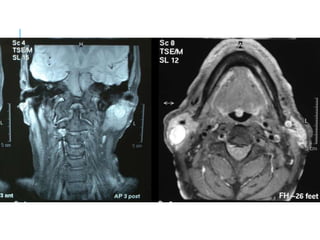

SALIVARY GLANDS

CT, MRI

SIALOGRA

PHY

injection of a small

amount of contrast

medium into the

salivary duct of a

single gland,

followed by

routine X-

ray projections

MRI AXIAL T1

MR- ANGIOGRAM